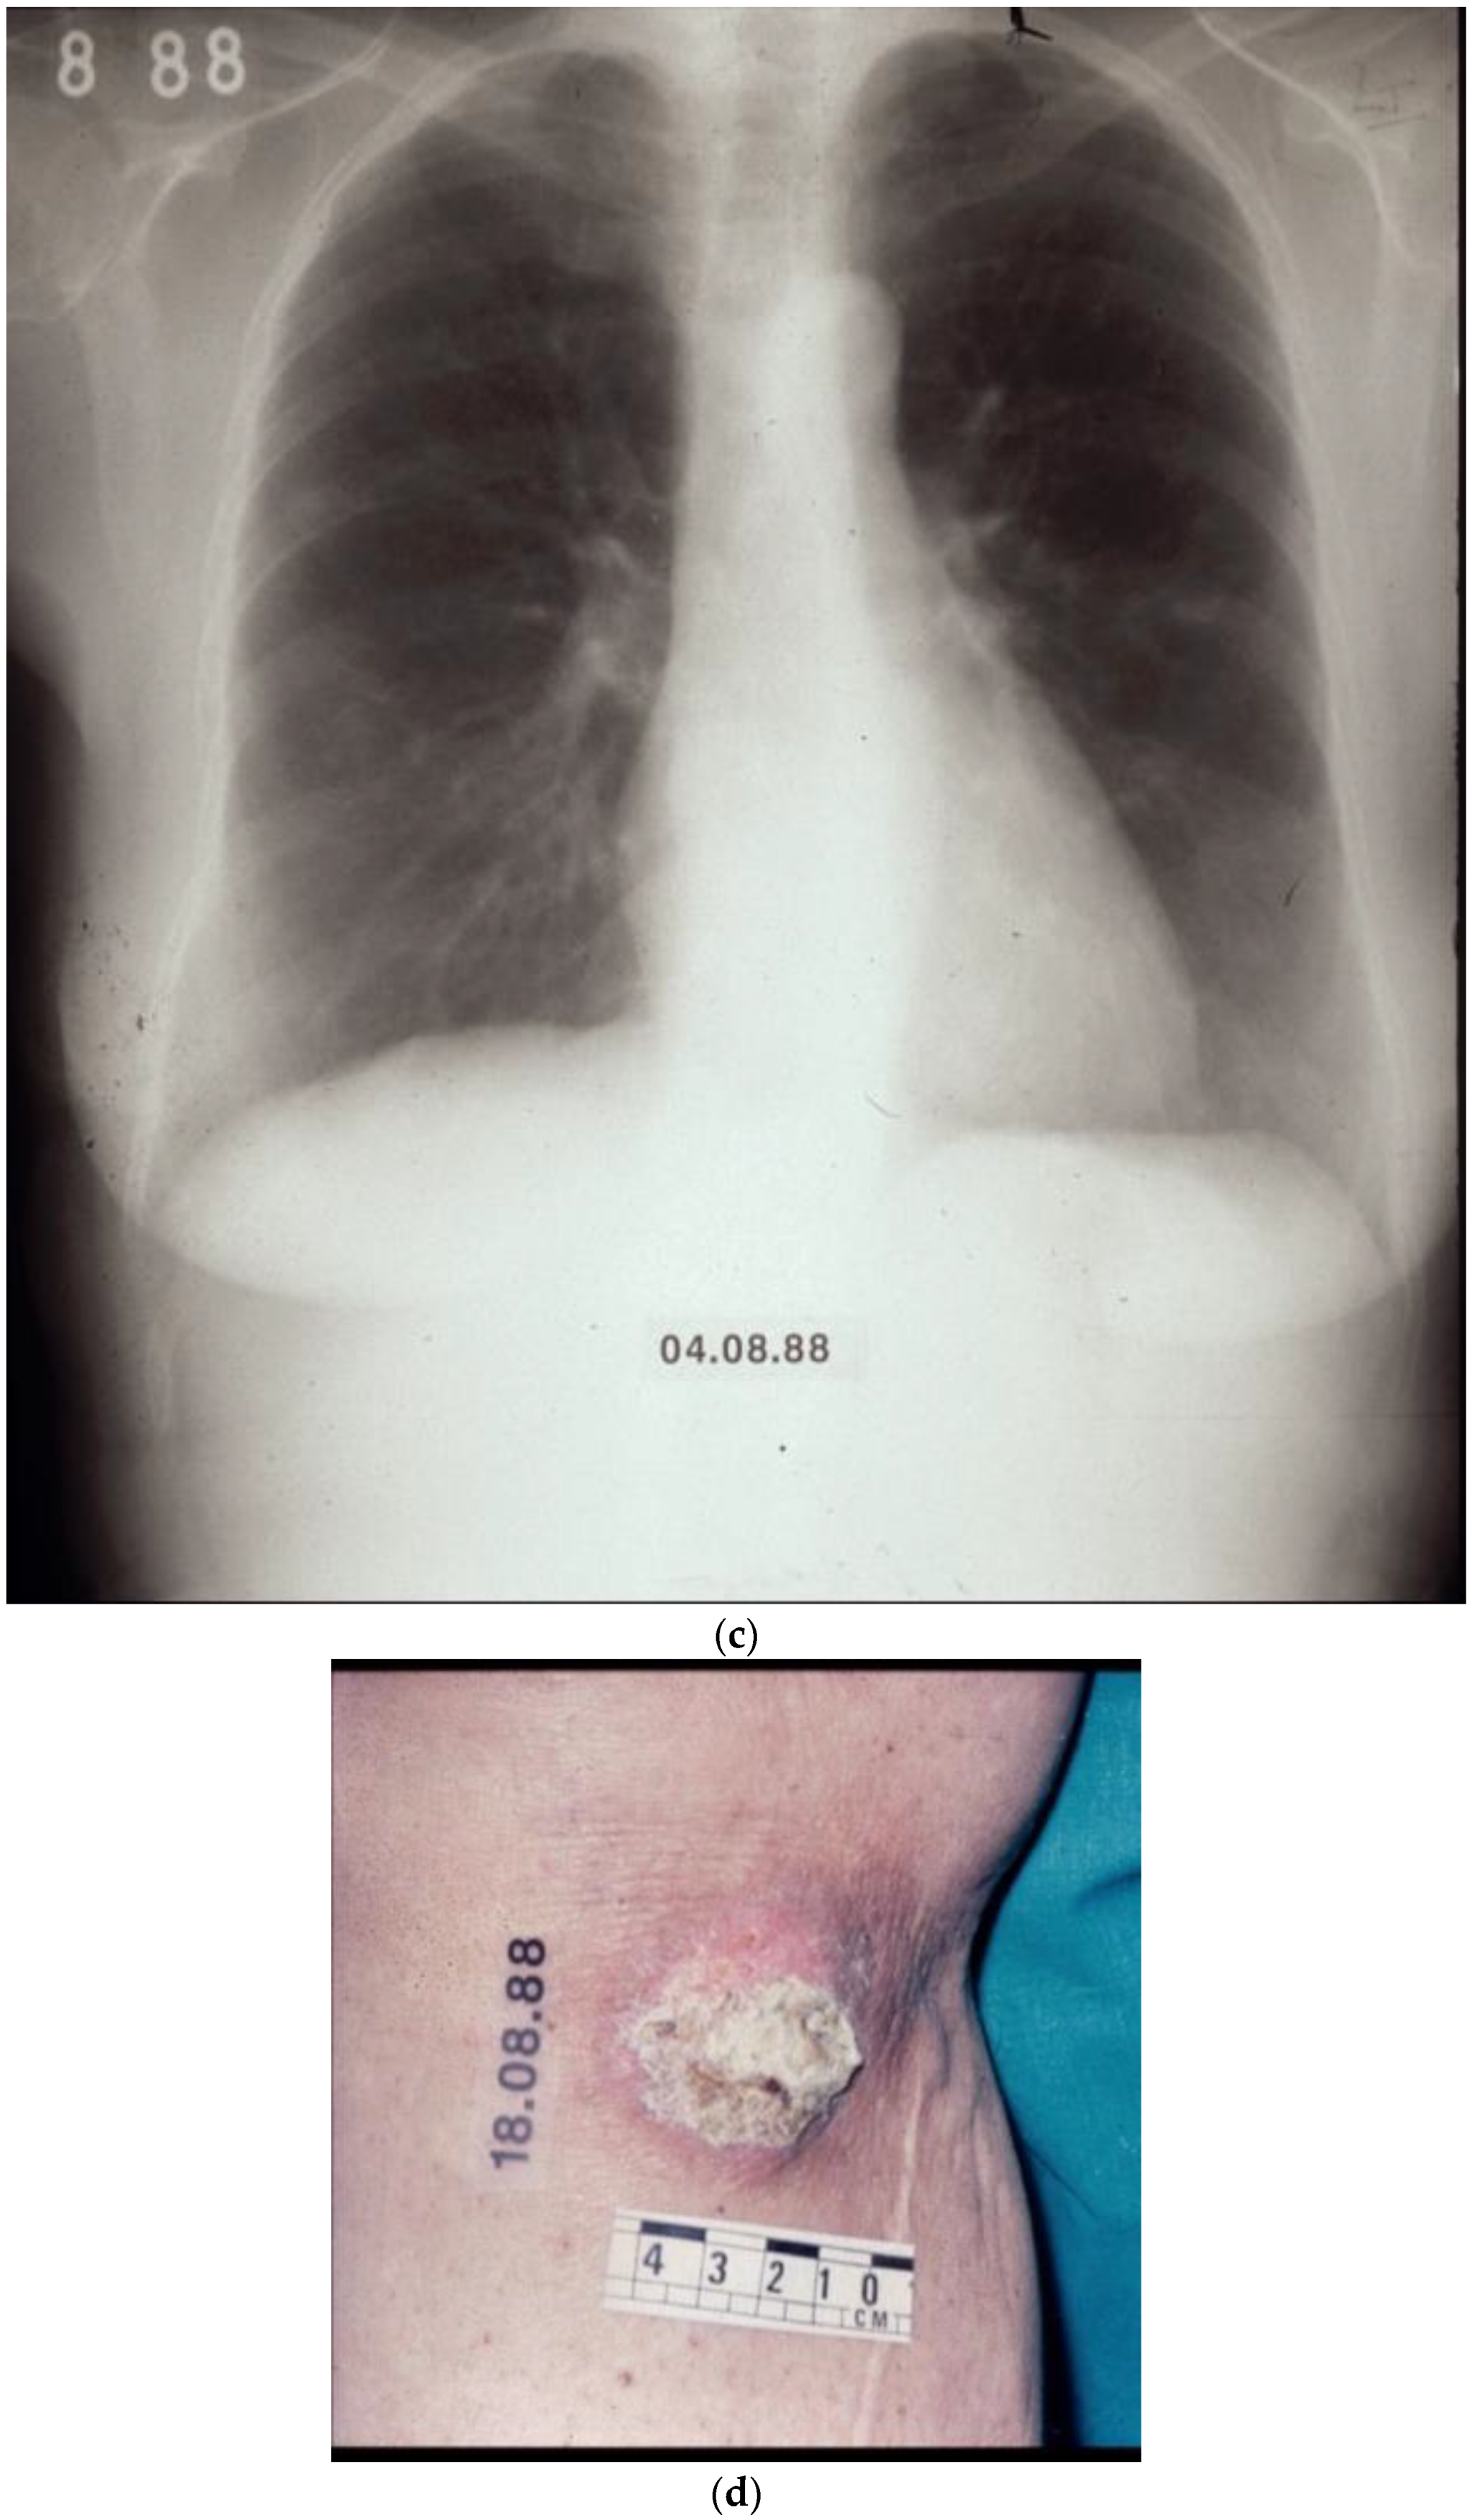

- Retsas, S.; MacRae, K.; Henry, K. Adjuvant Treatment for clinically apparent lymph node metastases (≥N1b) from melanoma: Single-institution experience from a cohort of 318 patients. Melanoma Res. 2002, 12, A15. [Google Scholar]

- Retsas, S.K. Clinical and histologic involvement of regional lymph nodes in malignant melanoma. Adjuvant vindesine improves survival. Cancer 1994, 73, 2119–2130. [Google Scholar] [CrossRef] [PubMed]